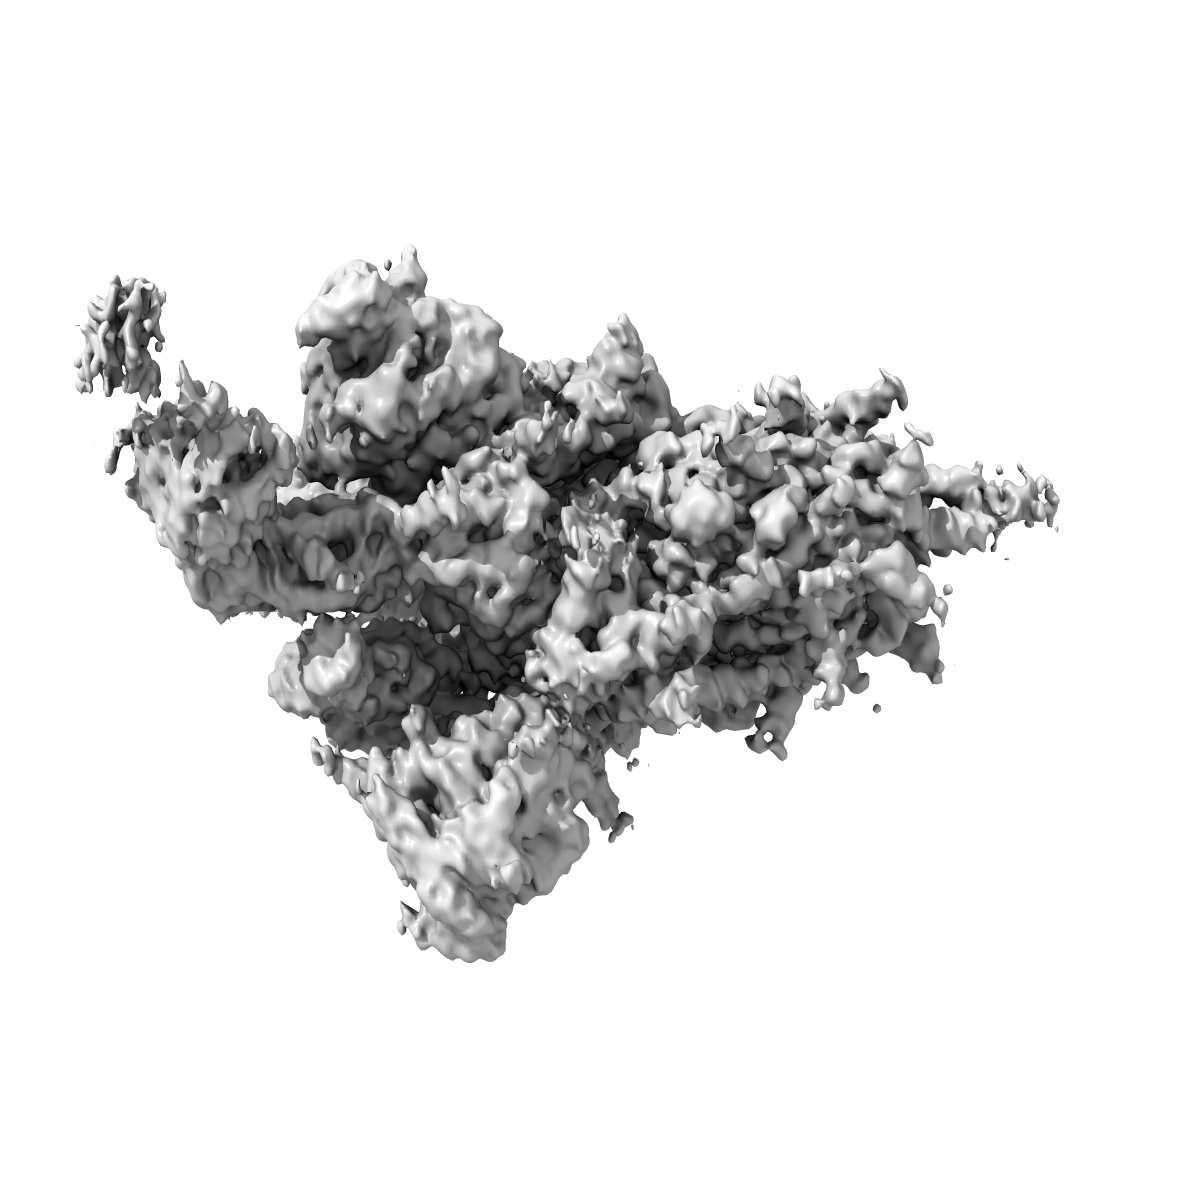

SARS-CoV-2 spike + IMCAS-123

Sample: Cryo-EM structure of SARS-CoV-2 spike + IMCAS-123

Deciphering a reliable synergistic bispecific strategy of rescuing antibodies for SARS-CoV-2 escape variants, including BA.2.86, EG.5.1, and JN.1.

Tong Z, Tong J, Lei W, Xie Y, Cui Y, Jia G, Li S, Zhang Z, Cheng Z , Xing X, Ma H , Deng L, Zhang R, Zhao X, Liu K, Wang Q, Qi J, Huang H, Song R, Su Z, Wu G, Lou J, Gao GF

(2024) Cell Rep , 43 , 114338 - 114338